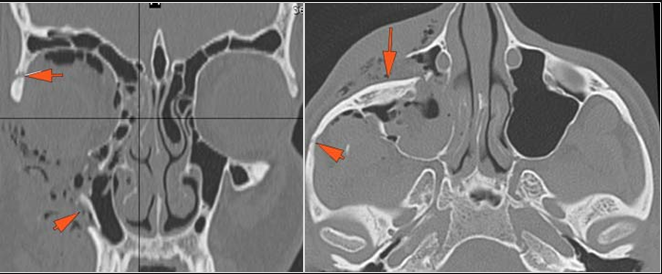

The medial, lateral and posterior maxillary walls are fractured.

The infraorbital rims and orbital process of the zygoma and/or frontozygomatic suture are fractured.

The the zygomatic arch, frontozygomatic suture or infraorbital rim are fractured.

The lateral wall of the orbit is fractured.

There is evidence of a subperiosteal hematoma along the medial wall, roof or floor of the orbit.